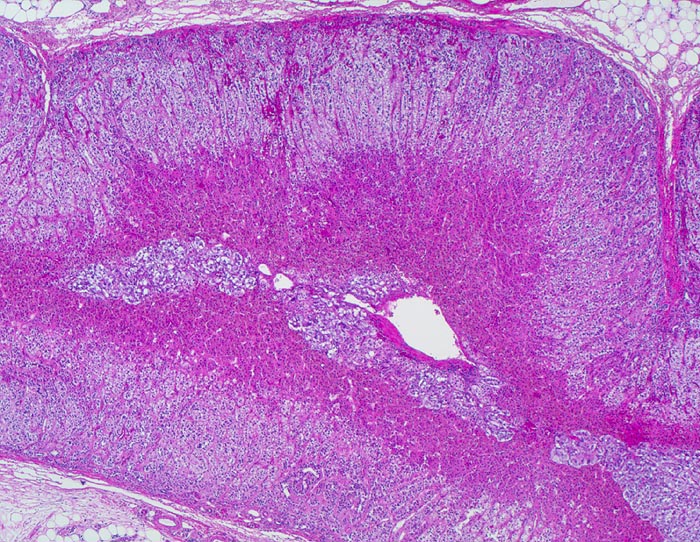

PathoPic – image database / PathoPic ID 4193 - normale Nebenniere

normale Nebenniere

Schichten der Nebenniere:

Zona fasciculata: Helles Areal der Nierenrinde. Bildungsort für Glucocorticoide.

Zona reticularis: Dunkles Areal angrenzend an das Nebennierenmark. Bildungsort für Sexualhormone.

Nebennierenmark

Das kombinierte Gewicht beider Nebennieren bei gesunden Erwachsenen Frauen und Männern beträgt ca. 8g. Die Dicke der normalen Nebennierenrinde beträgt 1mm (0.7-1.3mm).